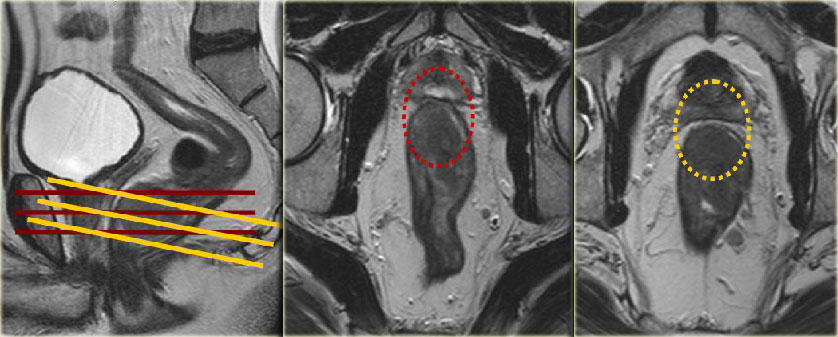

Мрт свища прямой кишки